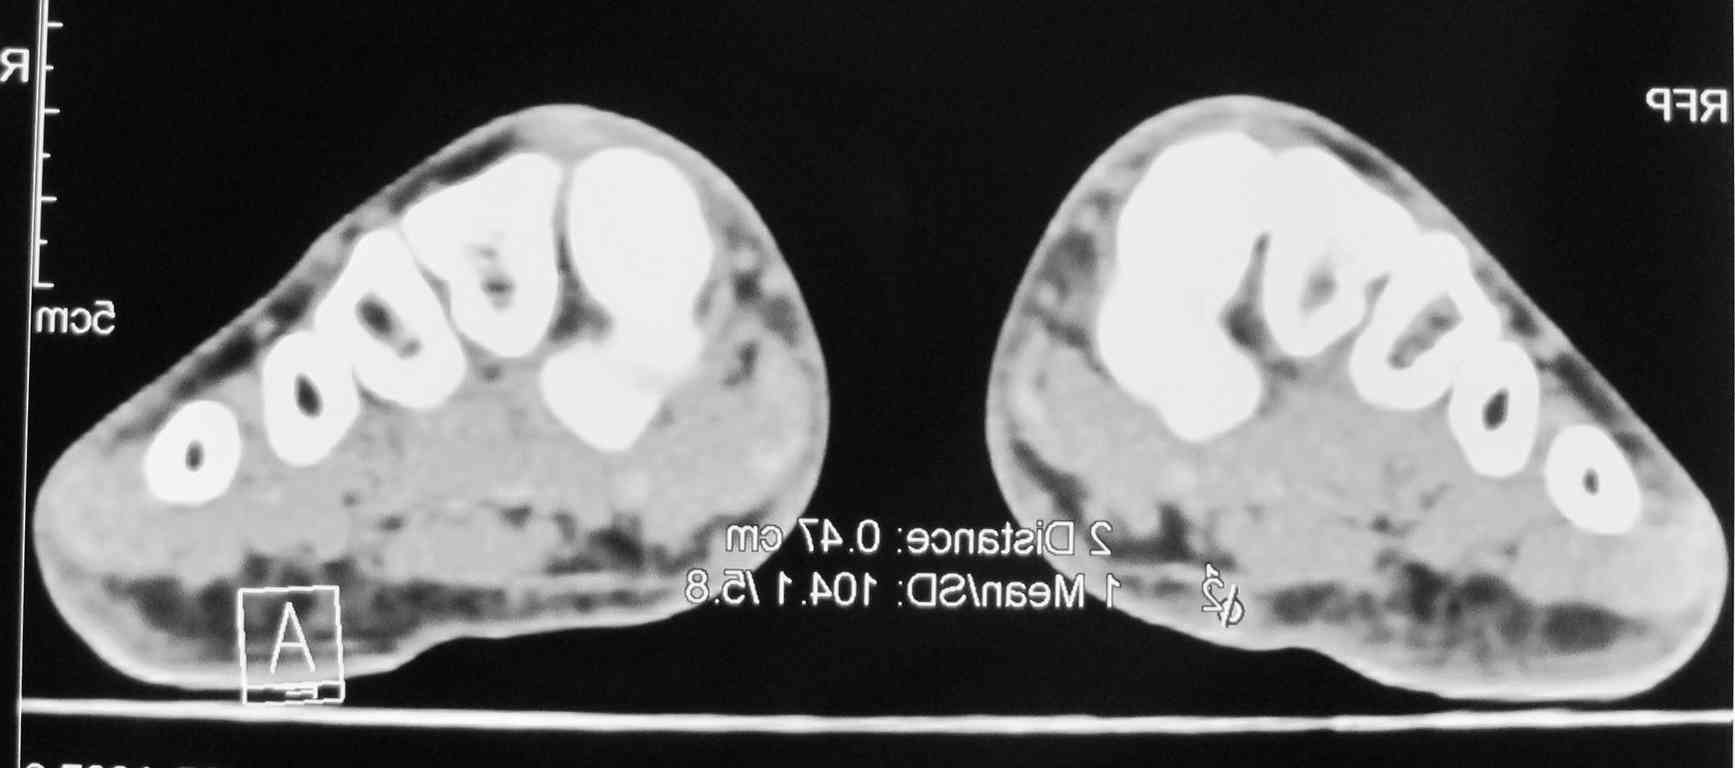

Мужчина 58 л. месяц назад наступил на камень, после того, как прошли боли, почувствовал уплотнение с медиальной стороны правой стопы.

Сделал КТ 02.11.2010 г.

Пальпаторно: определяется уплотнение размеры с горошину (0,3 Х 0,2), при пальпации безболезненно, малоподвижное. Кожные покровы в области уплотнения не изменены.